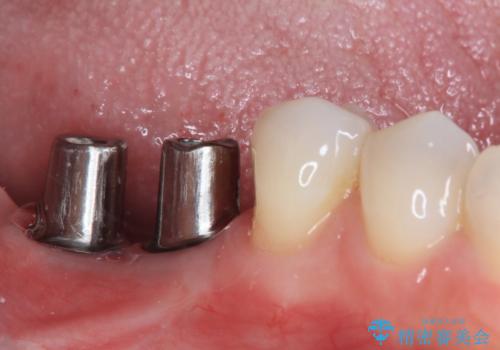

不正咬合で抜歯となった奥歯 インプラントによる咬合回復

- 近医にて抜歯が必要と言われたとこのことで来院された患者様です。

歯周病により抜歯が必要と診断されたとのことでしたが、実際は奥歯以外に歯周病の所見はなく、不正な咬み合わせにより負担が過剰となり、歯を支える歯槽骨が吸収している状態でした。

歯の周りの炎症が顕著であったため、抜歯後炎症が治まるのを待ち、咬み合わせが改善できる位置にインプラントを埋入することとしました。